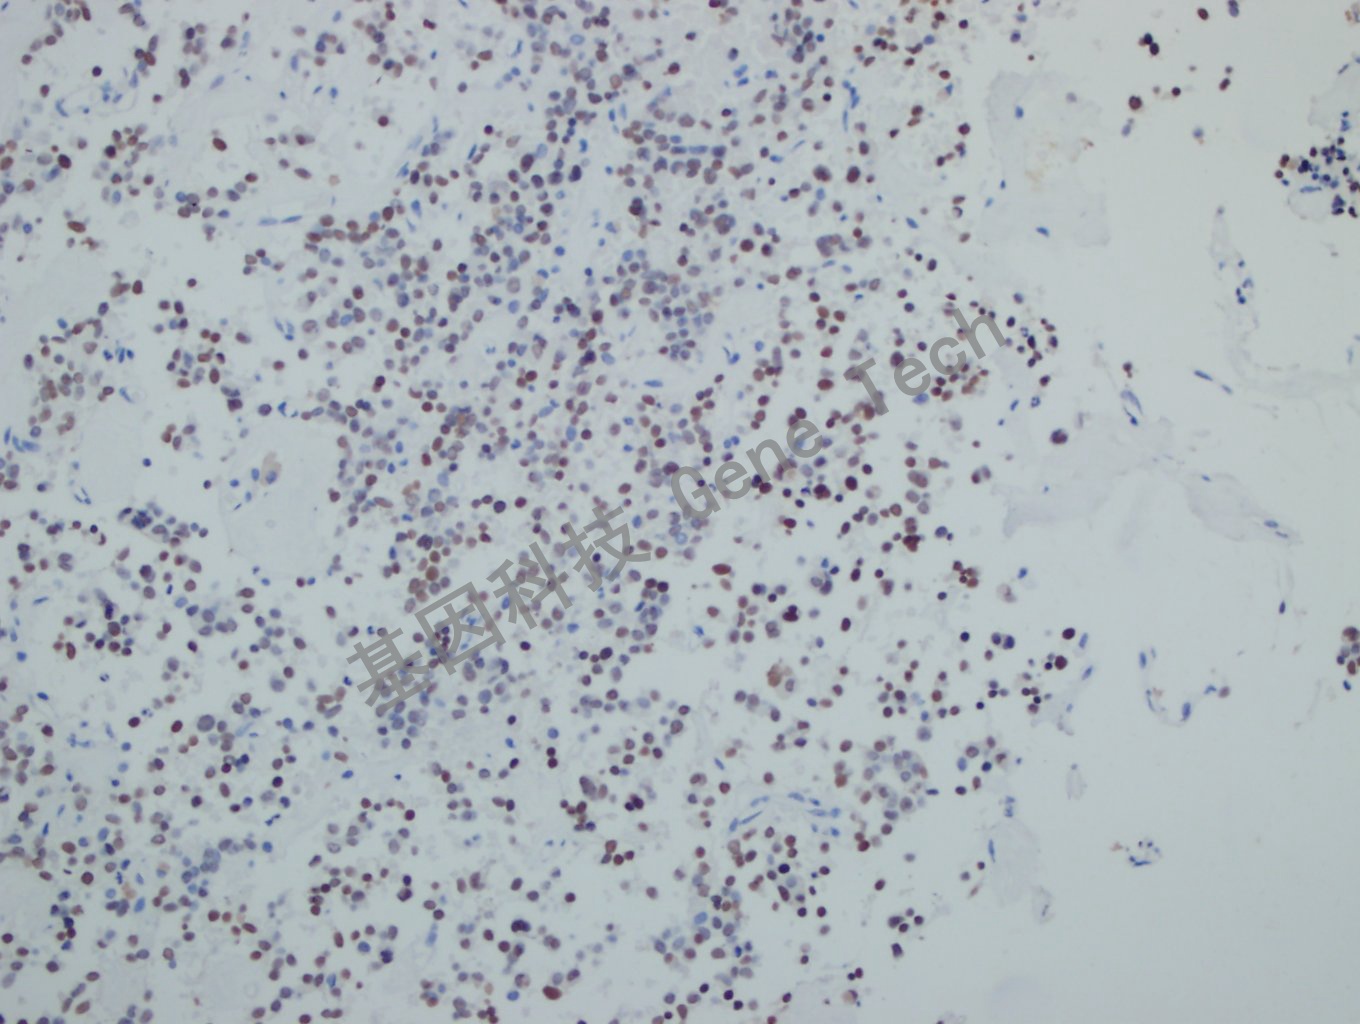

垂体瘤石蜡切片,用 PIT-1(GT2319)染色,细胞核阳性,DAB 显色。